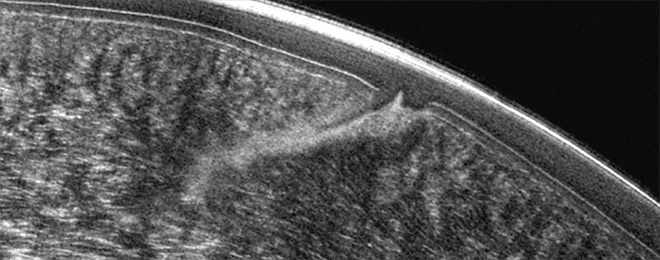

Pentacam® Cornea OCT TC